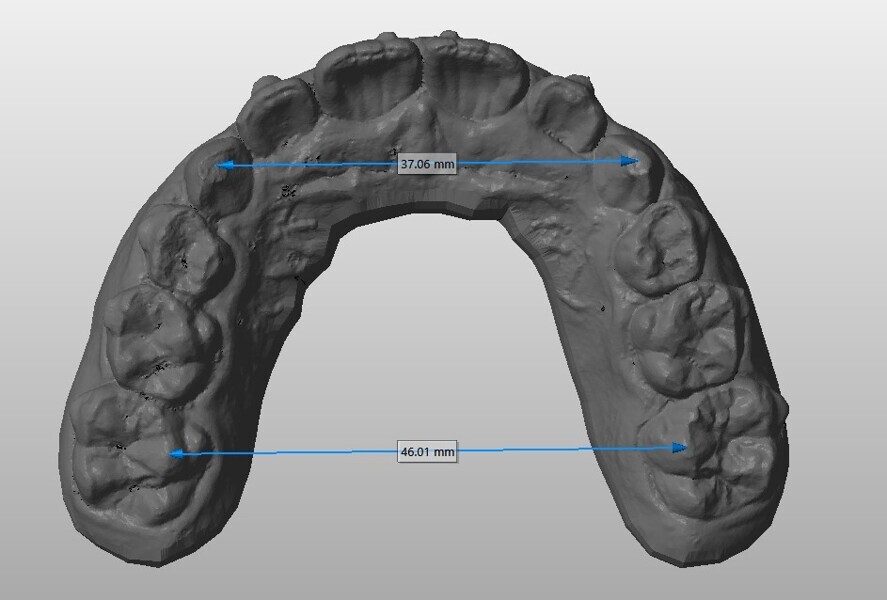

Analysis of the models in Autodesk Netfabb software (Fig. 12) showed regularisation of the arches and an increase in the maxillary inter-canine diameter of 2.61 mm and in the maxillary intermolar diameter of 2.29 mm. The superimposition of the arches at T0 and T1 (Fig. 13), performed using OnyxCeph3 (Image Instruments), was very significant and showed the shift from the initial arch shape and size to a wider shape posteriorly but with significant control of the maxillary incisor area.

Fig. 13: OnyxCeph3 superimposition. Blue = initial arch shape and size.